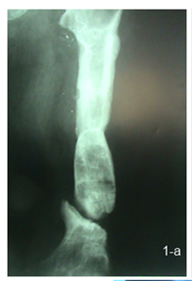

14 patients were operated by a 2 stage strategy including debridement at the fracture site through lateral approach with excision of all infected tissues and necrotic bone with no external fixation in the first session, then rest and parenteral antibiotic was given for 4 to 6 weeks and follow up with serial ESR & CRP were done before second session, 6 weeks after the first session; the second session was done through fixation by locked intra medullary nail with use of autogenous cancellous bone graft in patients with bone defects more than 2 cm (Figure 2 a, b).

Figure 2 a) Femoral infected non union after removal of implant in 1st stage. b) 2nd stage fixation by nail.